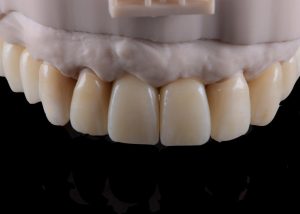

Completed provisional crowns, implant retained crowns and bridge, characterized with OPTIGLAZE color (GC) – Dental technician: Brad Groblar, Oral Dynamics, New Zealand. Fig. 14

Completed provisionals fitted onto the printed models to allow the refinement of the contact points and occlusal contacts. Fig. 15 (i, ii)